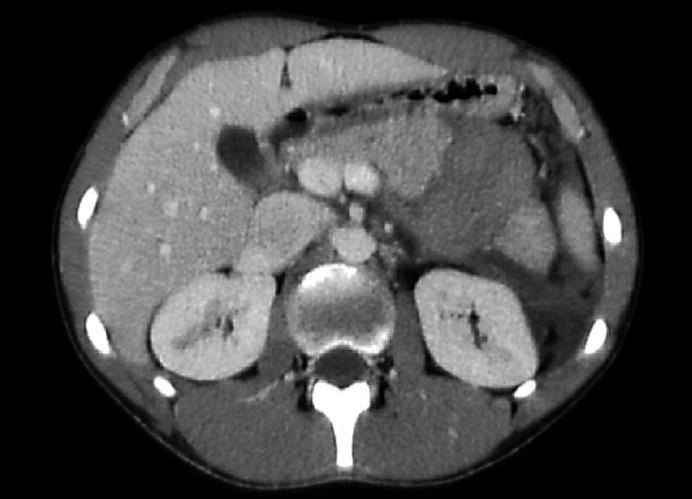

A 17-year-old rugby player was referred to our specialist unit after having been diagnosed with traumatic pancreatic transection, having presented 24 h after a sporting injury. Despite haemodynamic stability, at laparotomy he was found to have a diffuse mesenteric hematoma involving the large and small bowel mesentery, extending down to the sigmoid colon from the splenic flexure, and a large retroperitoneal hematoma arising from the pancreas. The pancreas was completely severed with the superior border of the distal segment remaining attached to the splenic vein that was intact. A distal pancreatectomy with spleen preservation and evacuation of the retroperitoneal hematoma was performed.

一名17岁的橄榄球运动员在运动损伤24小时后被诊断为创伤性胰腺横断,随后被转诊至我们的专科病房。尽管血流动力学稳定,但在剖腹手术中发现他有弥漫性肠系膜血肿,累及大小肠系膜,从脾曲向下延伸至乙状结肠,还有一个源于胰腺的巨大腹膜后血肿。胰腺完全横断,远端部分的上缘仍与完整的脾静脉相连。进行了保留脾脏的远端胰腺切除术并清除了腹膜后血肿。